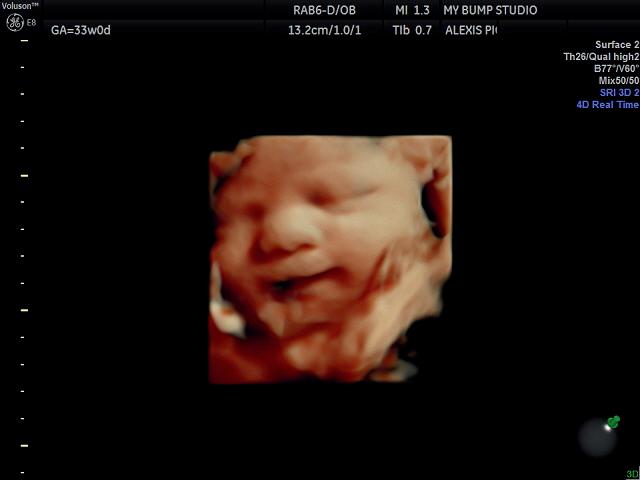

Aug. 9: Babypalooza Baby Expo. 10 a.m.-2 p.m. BJCC North Hall. 1160 Richard Arrington, Jr. Blvd. N., Babypalooza is a free, one-day expo offering seminars, baby gear demos and resources for new and expectant parents. babypalooza.com